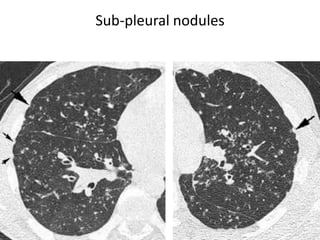

Sub-pleural nodules

Fissure nodules